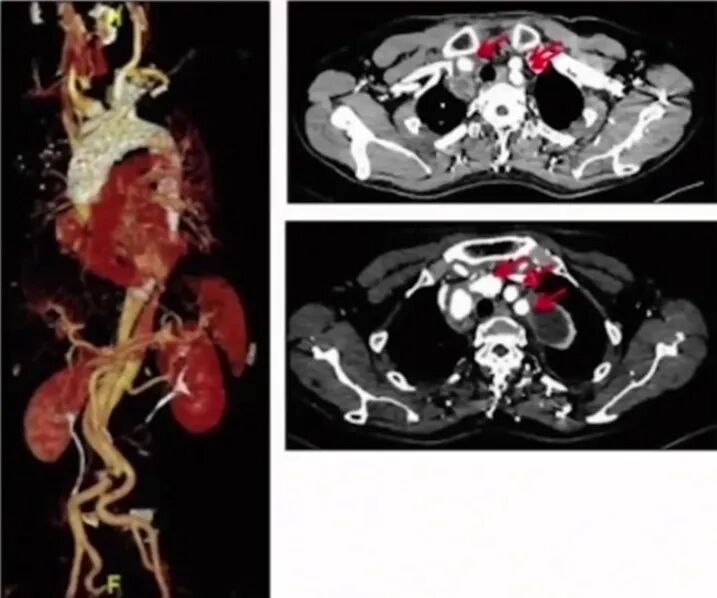

手术过程(四):自左肱动脉植入8F长鞘,抵至戈尔支架处,行左锁骨下动脉激光原位开窗。球囊扩张后,植入Lifestream覆膜支架。

术后造影:主动脉夹层消失,无明显内漏,弓上三分支动脉显影通畅。降主动脉真腔增大,显影通畅,内脏动脉显影良好。颅内动脉显影通畅,未见明显栓塞影像。

支架植入后:术后12个月随访:复查主动脉CTA可见主动脉重塑良好,弓上三分支显影通畅,无内漏形成。